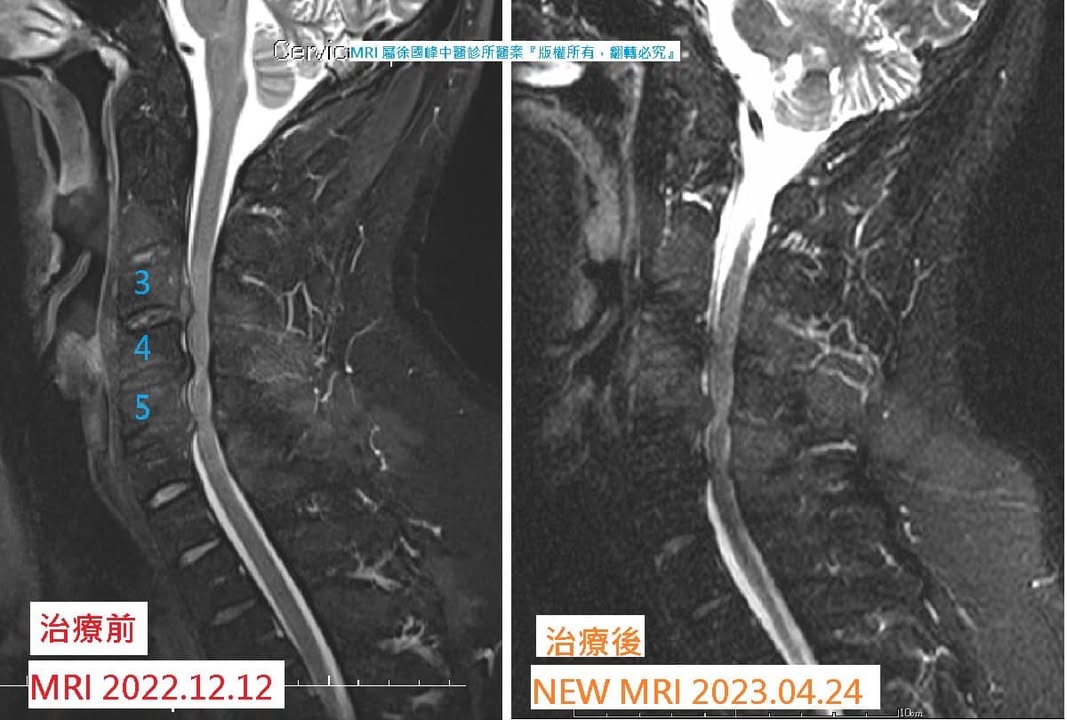

✅ 台南市新營區的朱先生,年紀約35歲,6個月前浮潛意外受傷,疼痛性質痠痛及麻痛,整天肩頸出現緊繃感,日常生活只要頭後仰明顯能感受壓迫神經,導致左右手肌肉不自主抖動。

❤️🩹來看診前,患者自述當初意外受傷後,這半年當中只要有頸椎向後仰的動作就會出現雙手有如電流般通過直達末梢後出現電到的感覺,看過新竹各大醫院的醫生,有2位醫生看過MRI後直接建議手術

🍀來診所治療的第3次左右就有很明顯的感覺,左右手肌肉會不自覺抖動的次數下降許多,焦慮及睡不著處亢奮的情況也減緩,治療至第9次時發現頸椎活動的角度又變得在更大一些,雙手麻痛到末梢的感覺都緩和很多,好轉程度直達到9成,超開心~~~

✅ 診斷:

1.頸椎過直

2.C3C4C5 輕微脊髓型頸椎病

📋治療時間:112.02.3~112.03.31 共15次